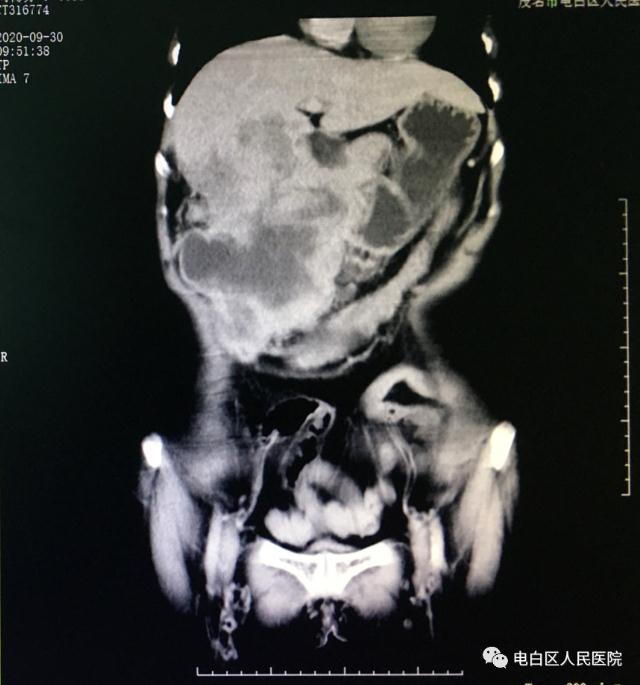

CT示肝區(qū)巨大占位

CT冠狀位示肝臟巨大占位,25厘米